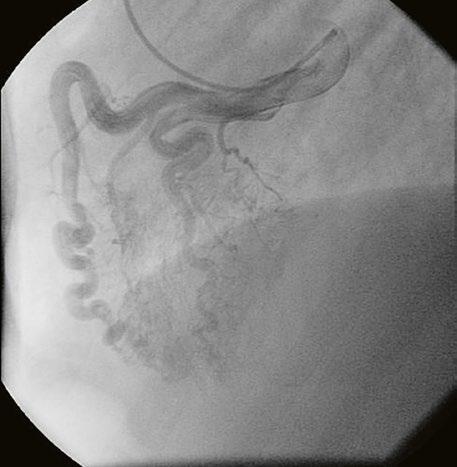

Supravalvární pulmonální stenóza a stenózy větví plicnice bývají součástí komplexních VSV (např. Fallotovy tetralogie) nebo syndromů (Williamsův syndrom, syndrom Noonanové, syndrom vrozené rubeoly, Alagillův syndrom aj.) (Obr. 45.39). Získané stenózy větví plicnice, ale i úplný uzávěr větve plicnice můžeme vidět po spojkových operacích podle BlalockaTaussigové (Obr. 45.40, Obr. 45.41). Pro zobrazení supravalvárních a periferních stenóz plicnice je optimální CT angiografie (Obr. 45.40, Obr. 45.41, Obr. 45.42, Obr. 45.43).

Obr. 45.42 CT angiografie. Dilatace kmene plicnice (PA), periferní stenóza v oblasti bifurkace a odstupu pravé větve plicnice (RPA) označena šipkou, odstup levé větve plicnice (LPA) je také lehce zúžen.

Obr. 45.43 CT angiografie, šipkou označena významná odstupová stenóza levé větve plicnice (LPA), lehčí stenóza odstupu pravé větve plicnice (RPA), kalcifikace v oblasti pulmonální chlopně

AO – aorta